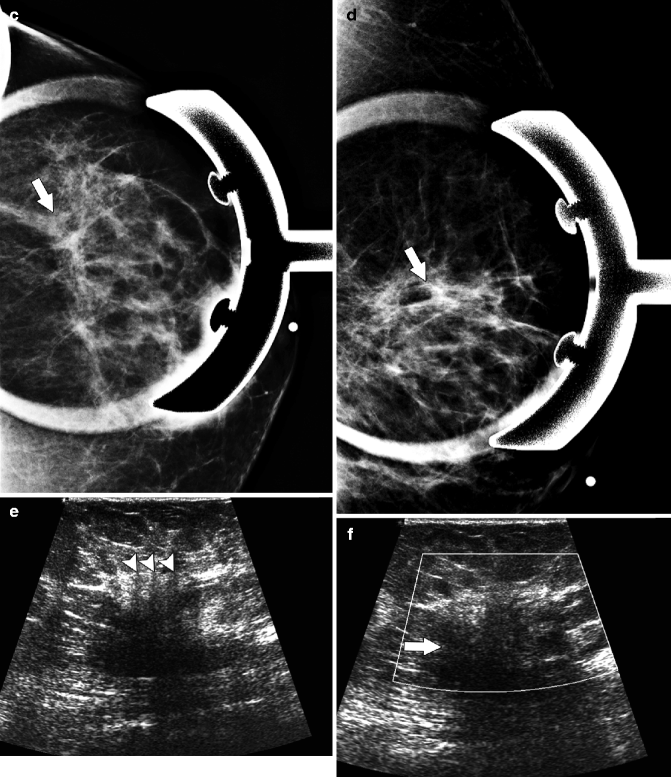

If you notice any symptoms of malignant breast tumors, your doctor will perform a series of tests to determine the cause. These tests may include a mammogram, ultrasound, or biopsy. A mammogram is an X-ray of the breast tissue, while an ultrasound uses sound waves to create an image of the breast. A biopsy involves removing a small piece of tissue from the breast for examination under a microscope.